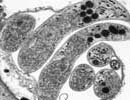

Cryptosporidium hominis TU502

Courtesy of Saul Tzipori, Tufts